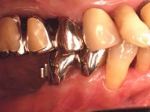

主訴-前歯部の咀嚼不全と審美障害。ブリッジ(固定橋義歯)のために歯を削ったところ

作業模型上のブリッジ

口腔内装着